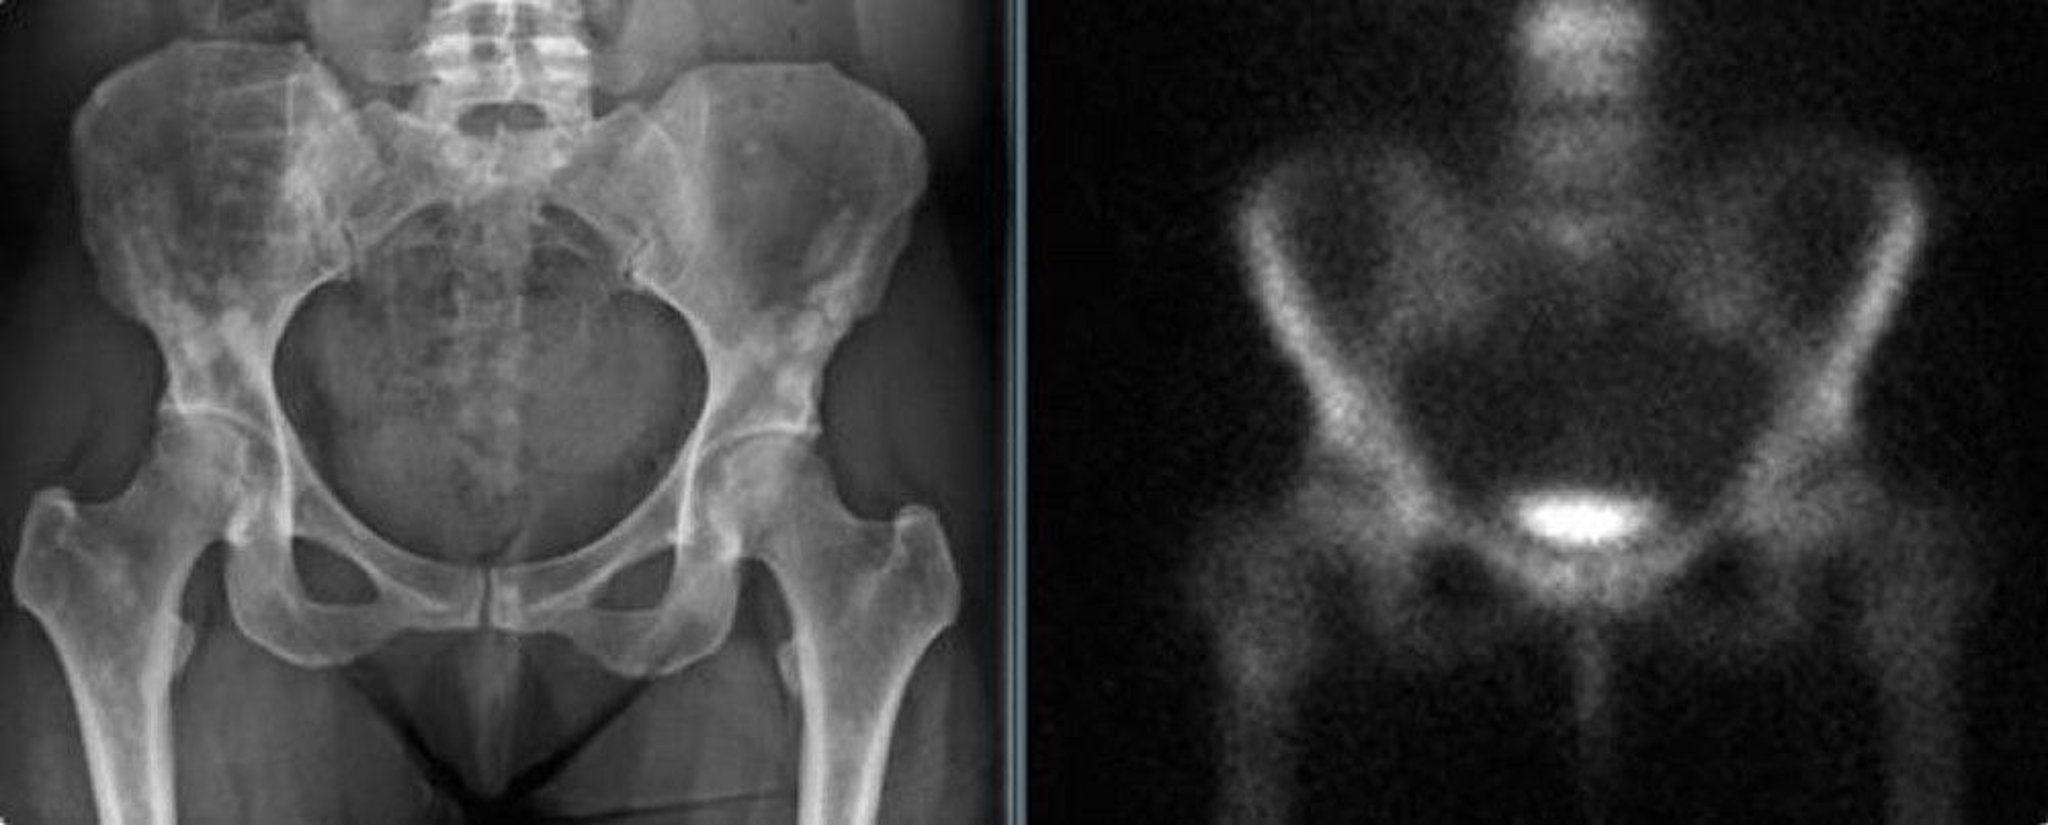

Osteopoikilosis of the Pelvis

The pelvic radiograph (left) shows osteopoikilosis of the pelvis in an adult woman. These densities could be mistaken for blastic metastases. The bone scan (right) shows no significant increased uptake.

Images courtesy of Michael J. Joyce, MD, and David M. Joyce, MD.